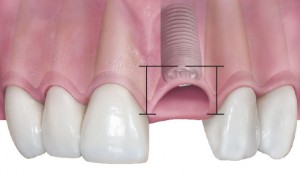

Основная цель имплантологического лечения….

Многие почему-то думают, что основная цель имплантологического лечения — это «вживить» импланты. Типа, добились интеграции, всё хорошо. И не совсем понятно, зачем кто-то заморачивается с синуслифтингом, остеопластикой, пластикой мягких тканей и т. д.?